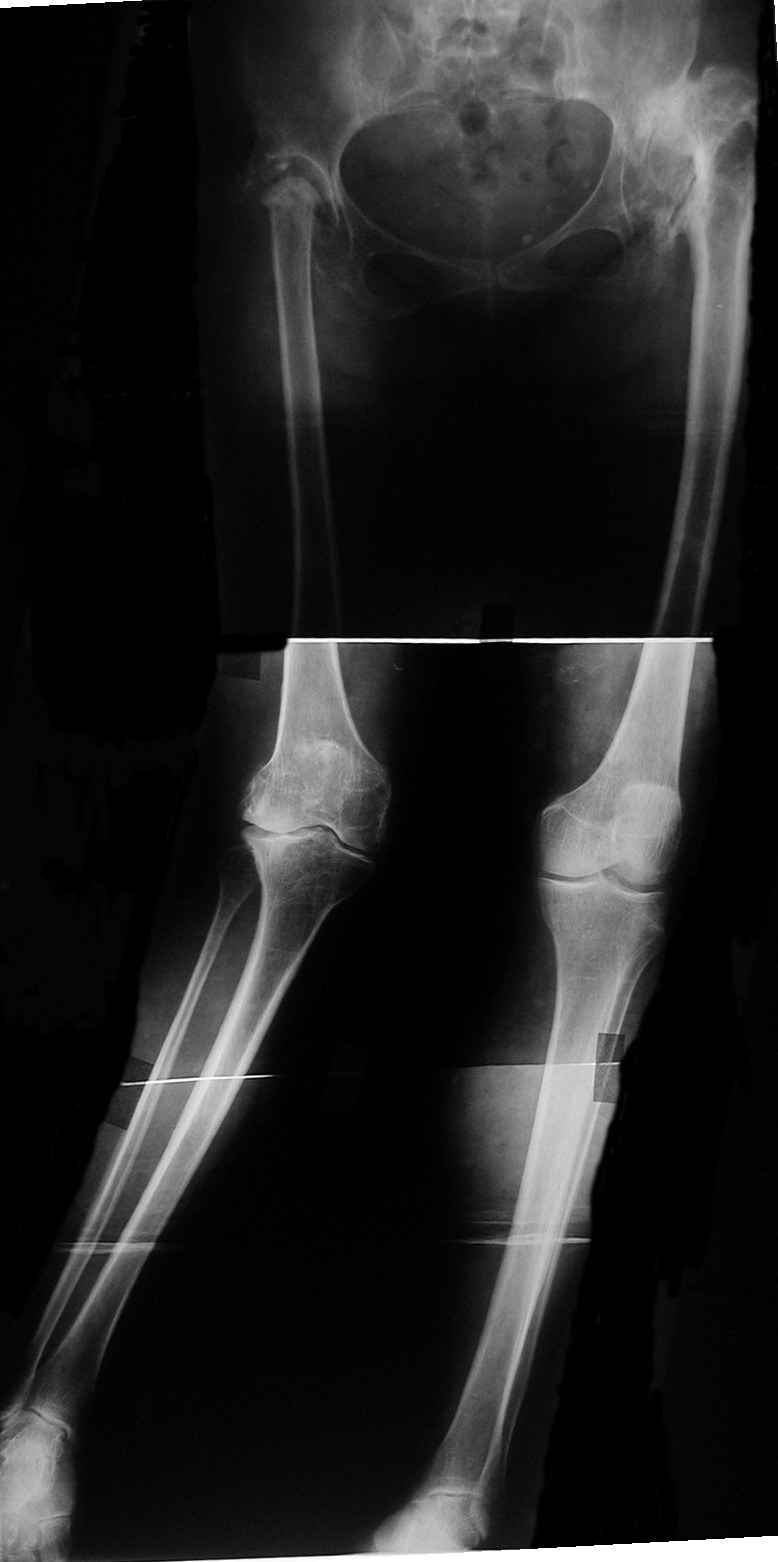

Уважаемые коллеги!В клинику для оперативного лечения поступила пациентка 61 года.

В анамнезе - открытое вправление врожденных вывихов обоих бедер в раннем детстве.

В 1972г. в институте выполнено эндопротезирование правого тазобедренного сустава протезом Сиваша.

Через год после установки эндопротез был удален ввиду развившейся нестабильности вертлужного компонента. В дальнейшем – неоднократные курсы консервативного лечения по поводу стойкого болевого синдрома с кратковременным положительным эффектом.

В настоящий момент пациентка поступила с жалобами на боль, деформацию правого коленного сустава. При осмотре вальгусная деформация на уровне правого коленного сустава 20 град., в нагрузке увеличивается до 30. Движения в правом коленном суставе болезненные, амплитуда 80/180 град. Опороспособность правой нижней конечности нарушена засчёт тотальной нестабильности правого коленного сустава. Стойкой контрактуры в неоартрозе на уровне правого тазобедренного сустава нет. В левом т/б суставе движения качательные, имеется сгибательно-приводящая контрактура, но сохранена опороспособность конечности.

1-м этапом планируем выполнить эндопротезирование правого тазобедренного сустава с использованием ножки типа Wagner. 2-м этапом – эндопротезирование правого коленного сустава. После восстановления функции суставов и опороспособности правой нижней конечности планируем выполнить эндопротезирование левого тазобедренного сустава.

Для т\б сустава, судя по снимку, не обязательно использовать Вагнер, можно любой с дистальной фиксацией (Цваймюллер или ЭС-тайпер)